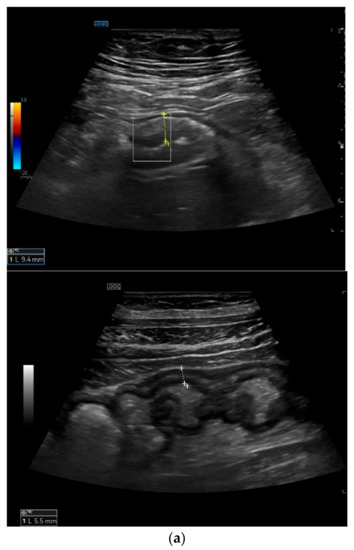

Bowel wall thickening (BWT): this parameter measures the distance from the interface between the lumen and the mucosa layer and the interface between the serosa layer and the proper muscle. It should be measured in the anterior wall of the bowel (or where it is better visible) in the longitudinal direction, avoiding haustrations and mucosal folds (see Figure 2) []. Bowel wall thickening is the most important and most used IUS parameter for the diagnosis of CD []. A cut-off value of 3 mm has shown a sensitivity and specificity of 89% and 96%, respectively. A cut-off value of 4 mm or more showed a sensitivity of 87% and a specificity of 98% [].

Figure 2.

Measurement of bowel wall thickening and bowel wall stratification: Bowel wall thickening is the most important IUS parameter in IBD patients. The most commonly used cut-off value is 3 mm. The bowel wall stratification can be focally or extensively disrupted or lost due to inflammation. (a) Bowel wall thickening with preserved layer stratification. (b) Bowel wall thickening with loss of stratification.

Bowel wall echo-pattern or bowel wall stratification (BWS): the bowel wall has a clearly defined multilayered aspect, but stratification can be focally or extensively disrupted or lost due to inflammation (see Figure 2). Disruption of stratification is associated to higher degrees of inflammation.